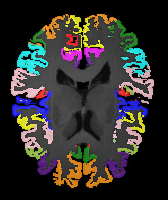

Moving Target Mono-0 Mono-5 DA-1 DA-5 Mono-200 Refer to caption Refer to caption Refer to caption Refer to caption Refer to caption Refer to caption Refer to caption Refer to caption Refer to caption Refer to caption Refer to caption Refer to caption Refer to caption Refer to caption

Image Manual Seg DA-1 Mono-21 DA-21 Mono-65 Refer to caption Refer to caption Refer to caption Refer to caption Refer to caption Refer to caption

Figure 2:  Examples of knee MRI registration (top) and brain MRI segmentation (bottom) results. Top: The first two columns are the moving image/segmentation and the target image/segmentation followed by the warped moving images (with deformation grids)/segmentations by different models. Bottom left to right: original image, manual segmentation, and predictions of various models. Mono-i𝑖i and DA-i𝑖i represent the mono- and DA models with i𝑖i manual segmentations respectively.

Results: All trained networks are evaluated using Dice overlap scores between predictions and the manual segmentations for the segmentation network, or between the warped moving segmentations and the target segmentations for the registration network. Tabs. 1 and 2 show results for the knee and brain MRI experiments respectively in Dice scores (%). Fig. 2 shows examples of knee MRI registrations and brain MRI segmentations.

Qualitative results: DA achieves more anatomically consistent registrations than the mono-networks on the knee (Fig. 2) and Brain MRI samples (see supplementary material).

Moving Target Mono-0 Mono-21 DA-1 DA-21 Mono-65 Refer to caption Refer to caption Refer to caption Refer to caption Refer to caption Refer to caption Refer to caption Refer to caption Refer to caption Refer to caption Refer to caption Refer to caption Refer to caption Refer to caption

Image Manual Seg DA-1 Mono-5 DA-5 Mono-200 Refer to caption Refer to caption Refer to caption Refer to caption Refer to caption Refer to caption

Figure 4: Examples of brain MRI registration (top) and knee MRI segmentation (bottom) results. Top: The first two columns are the moving image/segmentation and the target image/segmentation followed by the warped moving images/segmentations by different models. Bottom left to right: original image, manual segmentation, and predictions of various models. Mono-i𝑖i and DA-i𝑖i represent the mono- and DA models trained with i𝑖i manual segmentations respectively.